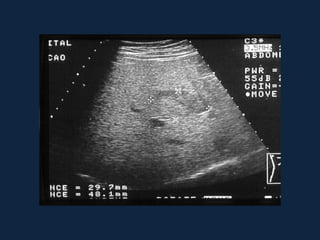

Cistos Simples

►Contornos bem definidos

►Atenuação baixa (semelhante a água, <20 UH)

►Sem realce ao meio de contraste

►Pode haver calcificação na parede do cisto

►Não há septações ou nodularidade mural

 Fase portal